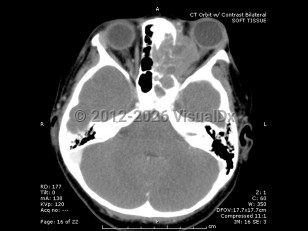

Orbital rhabdomyosarcoma - External and Internal Eye

Rhabdomyosarcoma is a rare childhood cancer that affects approximately 350 children per year in the United States, with 10% of cases involving the orbit. Rhabdomyosarcoma is the most common primary orbital tumor in childhood. Patients usually present between 5 and 10 years of age, with boys having a higher incidence than girls.

Orbital rhabdomyosarcoma develops from undifferentiated mesenchymal cells that have the capacity to become striated muscle. There are several histopathologic types, including embryonal (the most common form) and alveolar (which carries the worst prognosis).

Proptosis is the most common presenting sign and may develop over the course of just a few days or a month. Often there is a history of recent trauma upon presentation of the tumor, which may lead to confusion with the diagnosis. Orbital rhabdomyosarcoma sometimes presents with strabismus or as a localized eyelid or conjunctival mass.